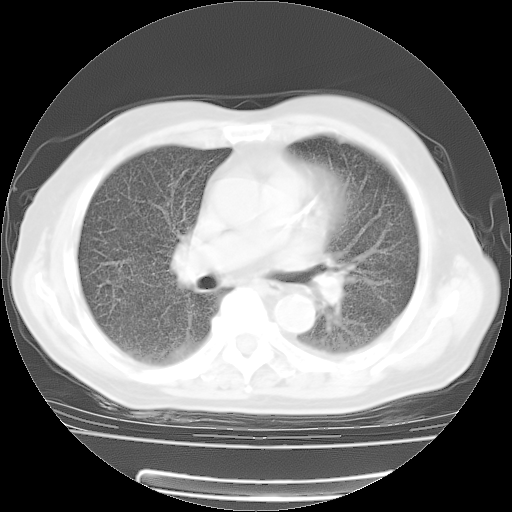

肺部CT平扫未见异常。